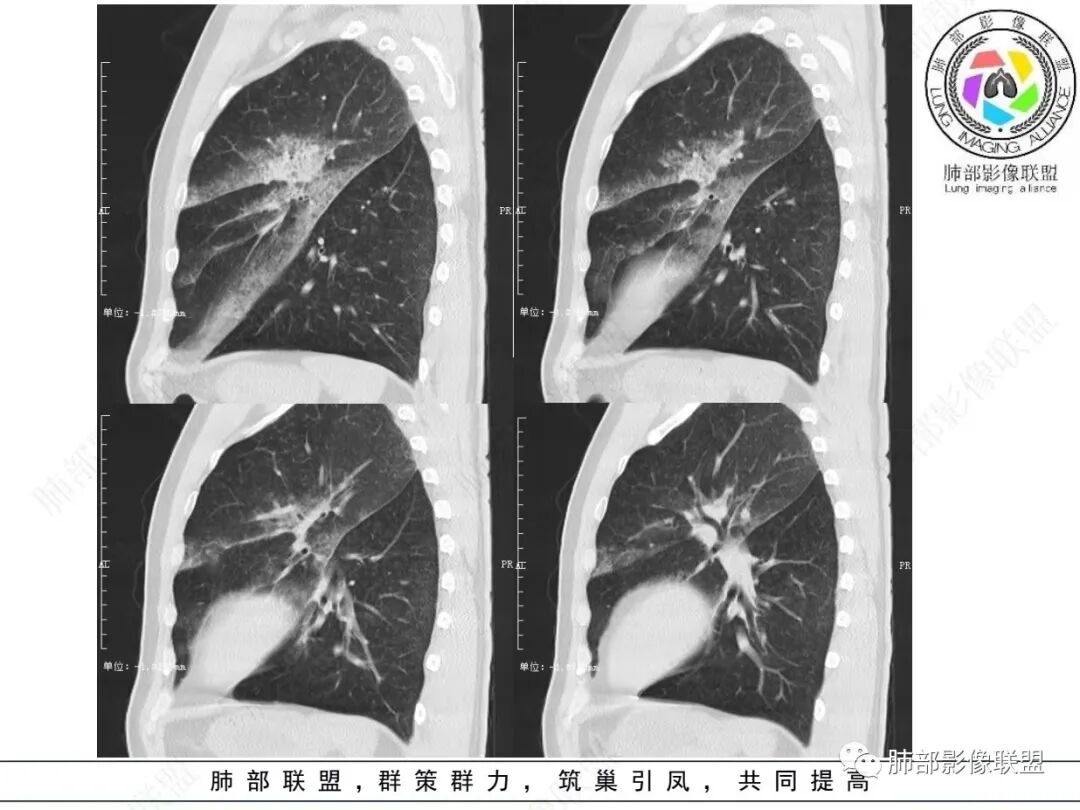

2.左肺上叶大片状混合密度影,未见空洞,实变影主要位于胸膜下,长轴与胸膜平行,实变区内部密度不均、其内可见多发小斑片状低密度影,磨玻璃影多位居肺门一侧,可见网格,磨玻璃影边界多可分辨,重力分布趋势。病灶区支气管显示较为通畅,进入外围实变区渐至消隐。病灶轻度不均匀低强化,病灶区肺动脉显示较良好,未见破坏。

双肺广泛分布微小磨玻璃密度结节影,腺泡结节样分布,密度大小较为均匀一致。

3. 综上,患者中年男性,长病程,影像上磨玻璃/实性混合密度,边界可分辨,重力分布趋势,支气管通畅,穿行血管较为完好,较为符合典型粘液腺癌或腺癌影像学表现。如影像上进行性进展且出现多肺段多肺叶飘散磨玻璃结节,则更具判断价值!